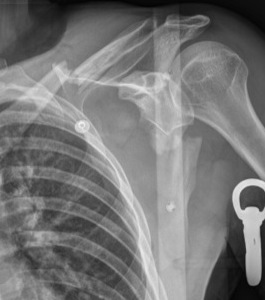

Scapular neck fracture with clavicle fracture